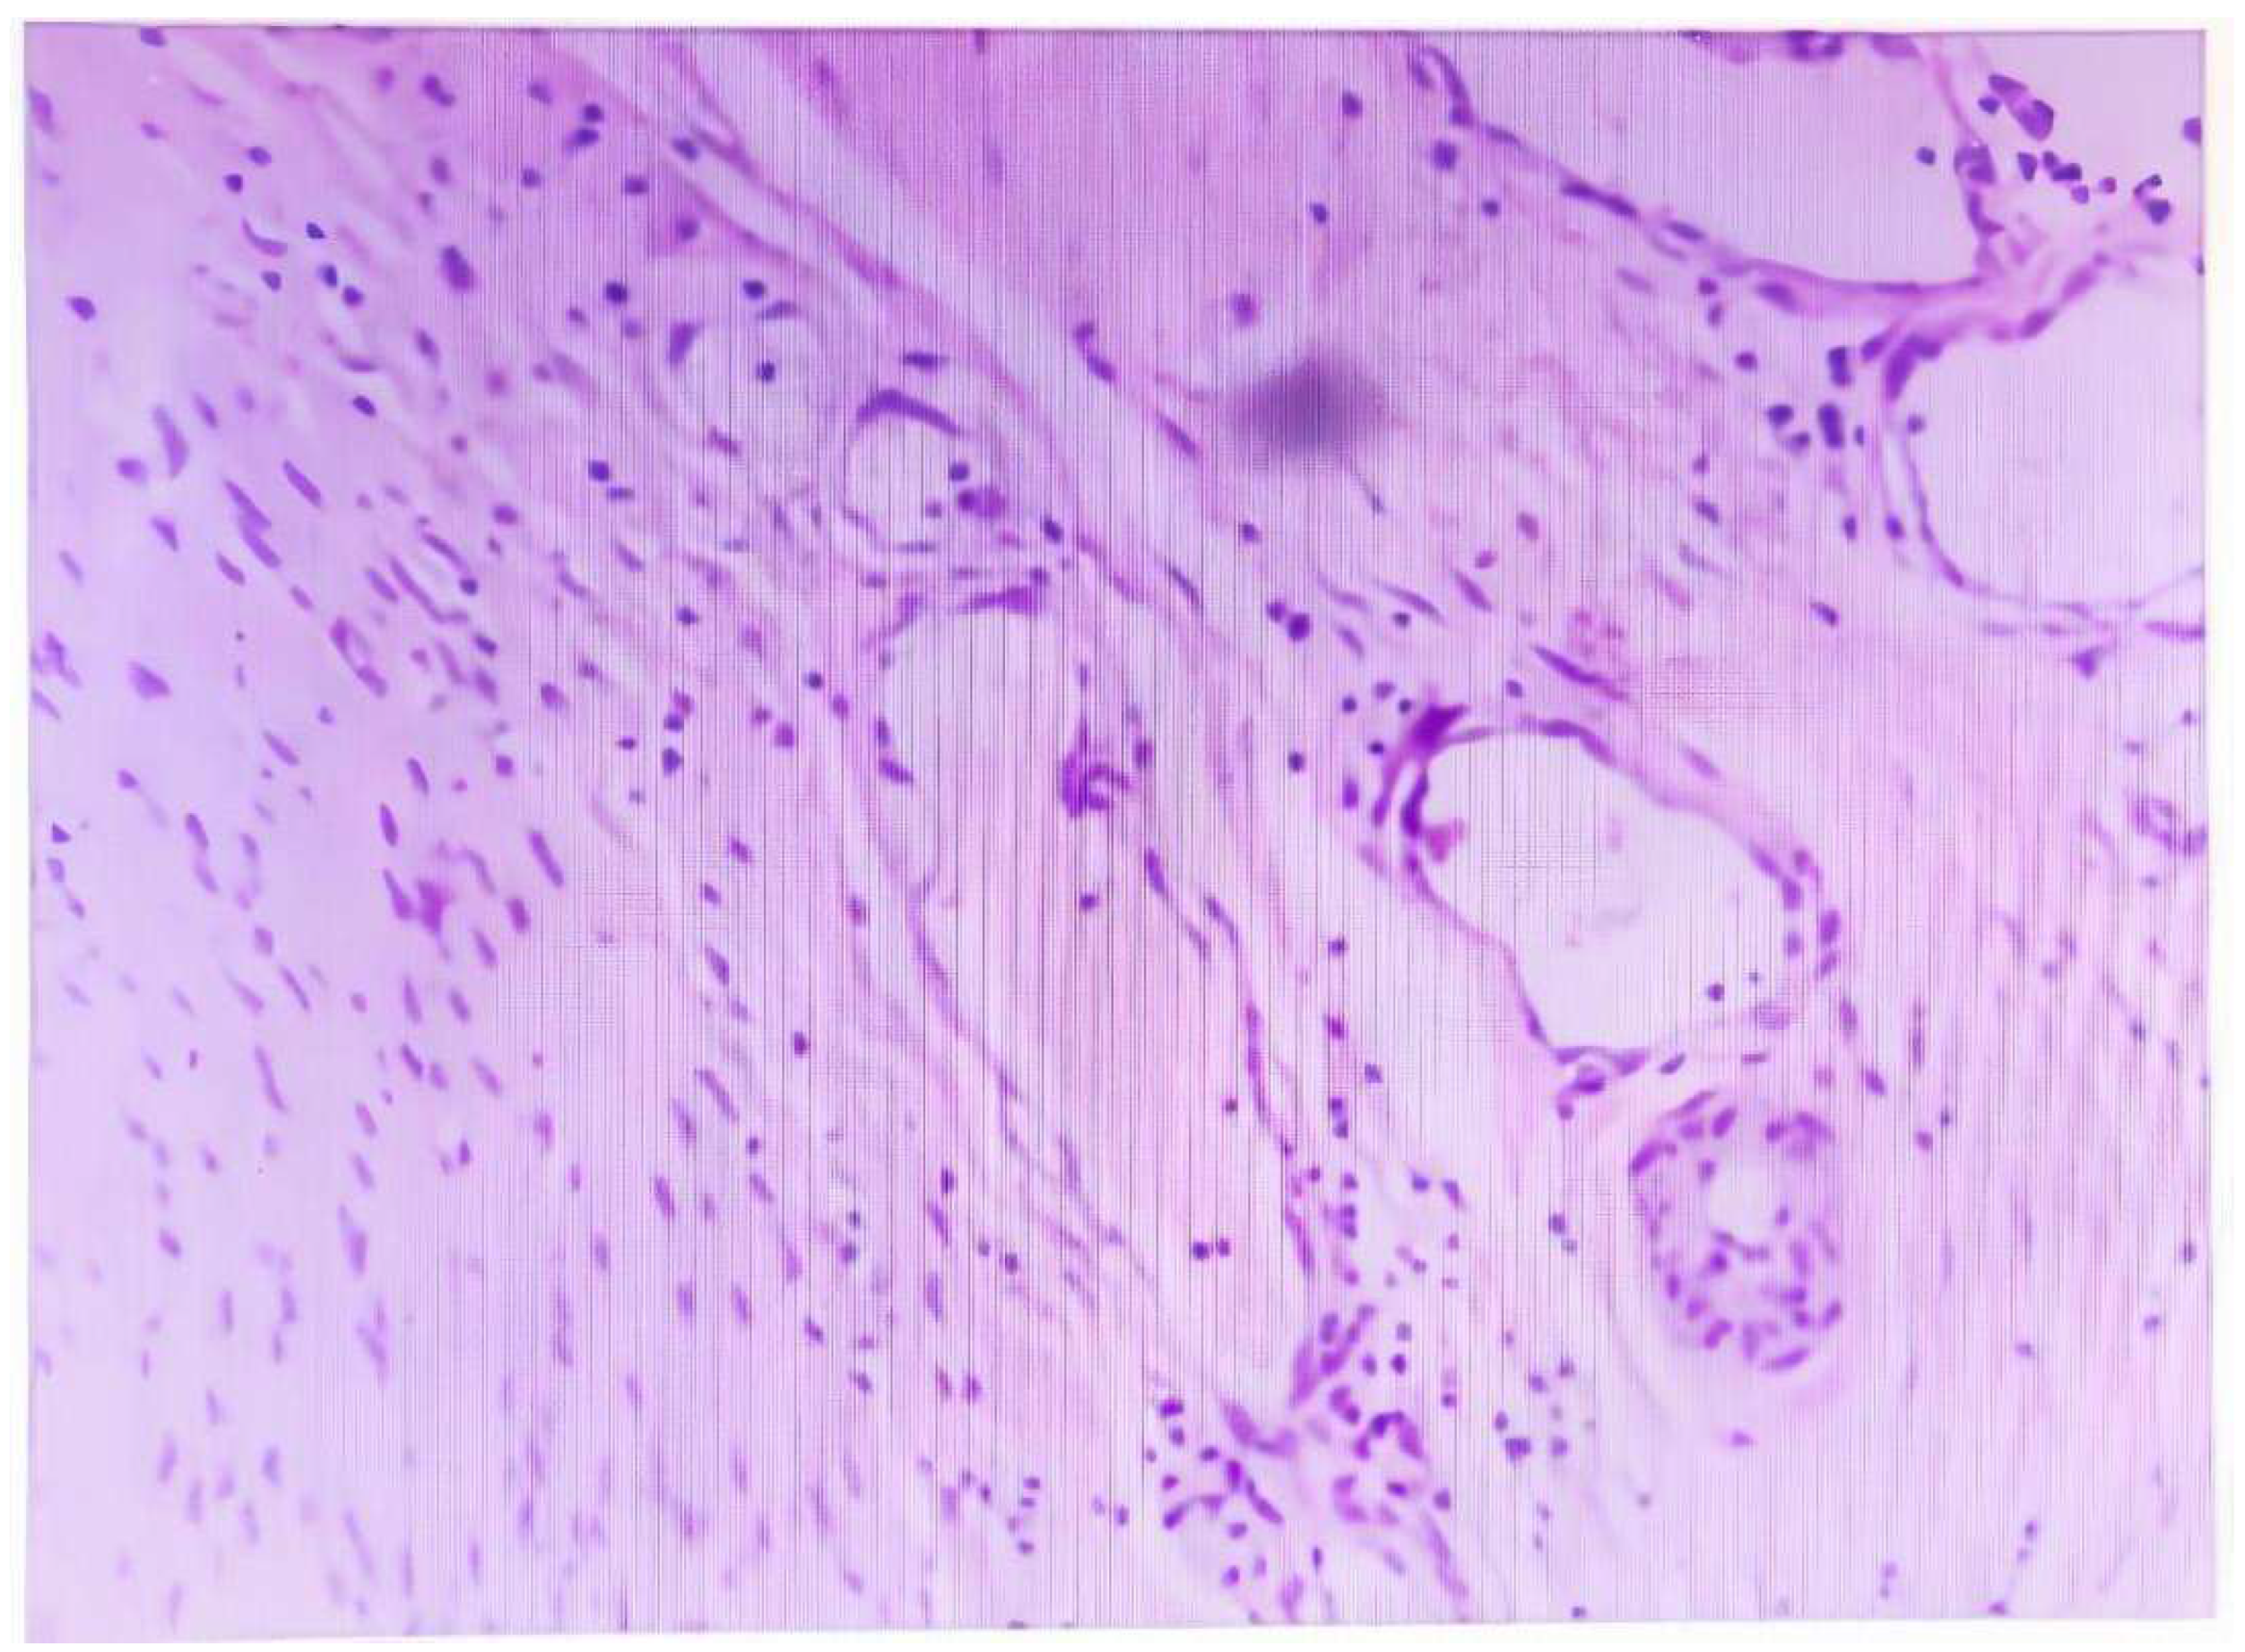

In terms of pathology, the cut surfaces of GAS gross specimens may present yellow or gray-white, with typical honeycomb-like changes, densely filled with mucous-containing cysts of varying sizes, with diameters of 0.5 – 1.0 cm. The morphologic criteria for distinguishing GAS were defined as a tumor showing clear and/or pale eosinophilic and voluminous cytoplasm, with distinct cell borders [7] (Figure 2). IHC markers HIK1083 and MUC6 may help to confirm the gastric-type differentiation [8]. However, in most parts of the world, HIK1083 is not commercially available for use [9]. P16, ER, and PR are mostly negative, with only a few cases showing positivity [10]. Additionally, CDX2 and PAX8 are partially positive [11], and in some cases, P53 shows mutant expression [12]. The IHC results of our case were generally consistent with the aforementioned pathological features.

Figure 2. The representative morphologic photo of this case. Clear and/or pale eosinophilic and voluminous cytoplasm, with distinct cell borders.